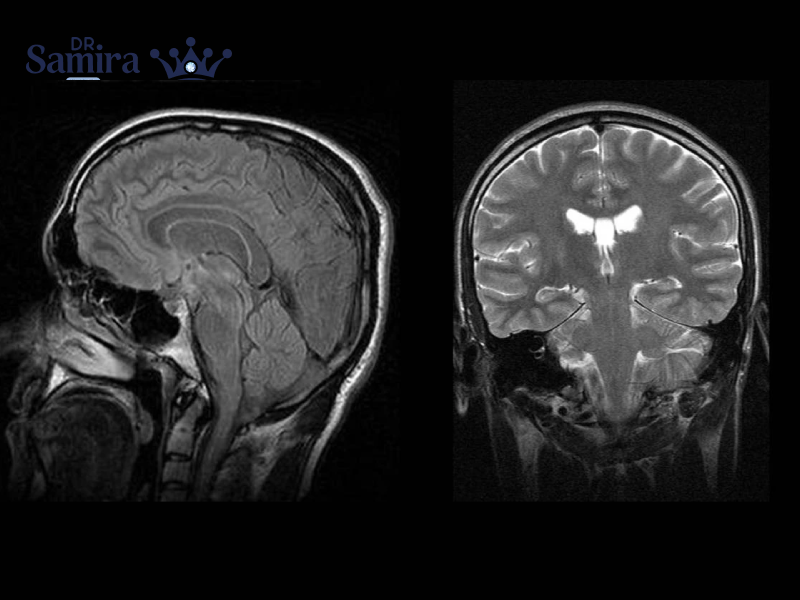

کیست آراکنوئید مغز نوعی حفره پر از مایع مغزی ـ نخاعی است که بین لایههای پرده...